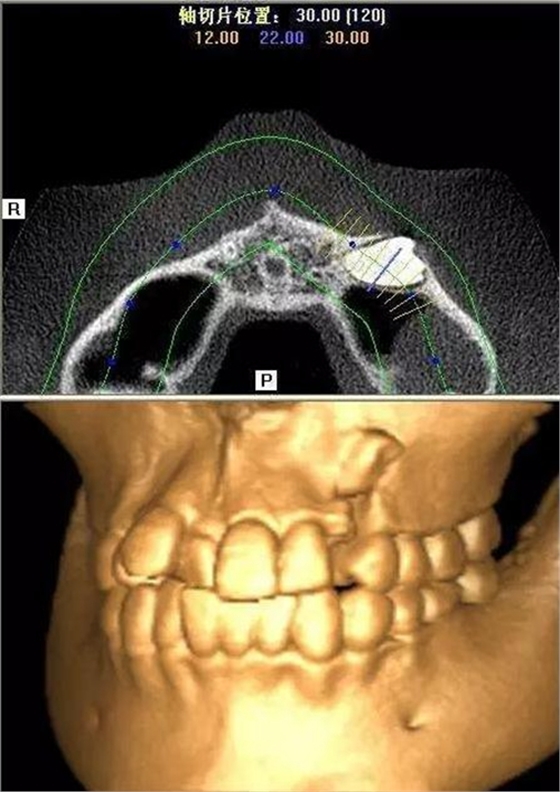

本案:患兒,女,14歲,因牙齒矯正來(lái)院,檢查見(jiàn)83滯留,43未見(jiàn)萌出,拍片發(fā)現(xiàn):43埋伏阻生于31、41、42根尖下方,按照正畸診療計(jì)劃,擬行43拔除術(shù)。

CBCT顯示